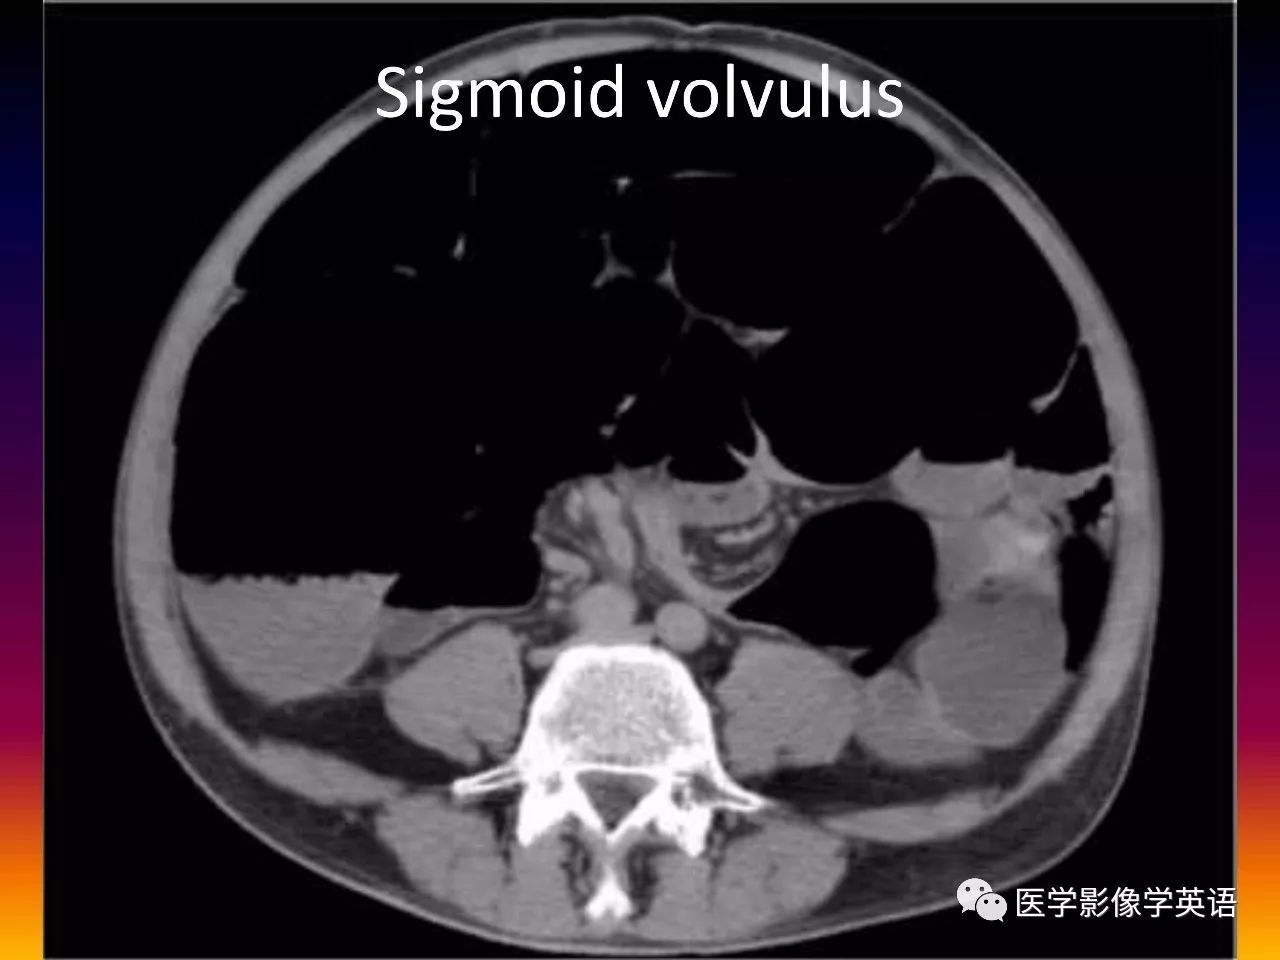

88. Sigmoid volvulus

89. Sigmoid volvulus

45. Volvulus Gastric volvulus Organo-axial Greater curvature above lesser curvature Mesentero-axial Gastric antrum above gastric fundus Midgut volvulus Malrotation (SMV to the left of SMA) Whirl sign Colonic volvulus Sigmoid Whirl sign Cecal Whirl sign